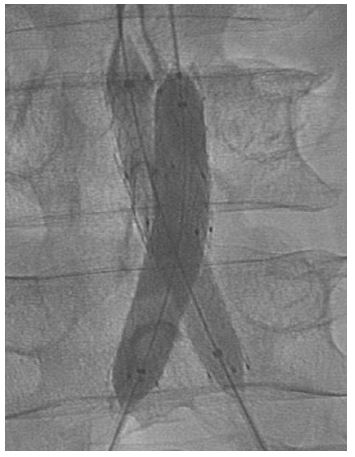

Male patient, 76 years, with a history of Endovascular repair of Aortic Abdominal Aneurysm (EVAR) evolved with endoprosthesis right limb occlusion, associated with disabling claudication. Due to this important symptom, the patient was scheduled to undergo an endovascular procedure with right limb recanalization and implant of Wrapsody 14×80 mm at the infra-renal aorta and right common iliac artery, followed by the implant of Wrapsody 14×80 mm at the right common iliac artery and another Wrapsody 16×80 mm at iliac bifurcation (Snorkel Technique). The left limb was also treated to perform a Kissing Stent with the implant of Viabahn 13×100 mm. (Figure 2). The patient was discharged from the hospital first day post-operative and 1 one-month follow-up showed endoprosthesis patency and no endoleaks with complete resolution of the previous disabling claudication.

Figure 2: Right limb recanalization and implant of Wrapsody 14×80 mm at the infra-renal aorta and right common iliac artery, followed by the implant of Wrapsody 14×80 mm at the right common iliac artery and another Wrapsody 16×80 mm at iliac bifurcation (Snorkel Technique).